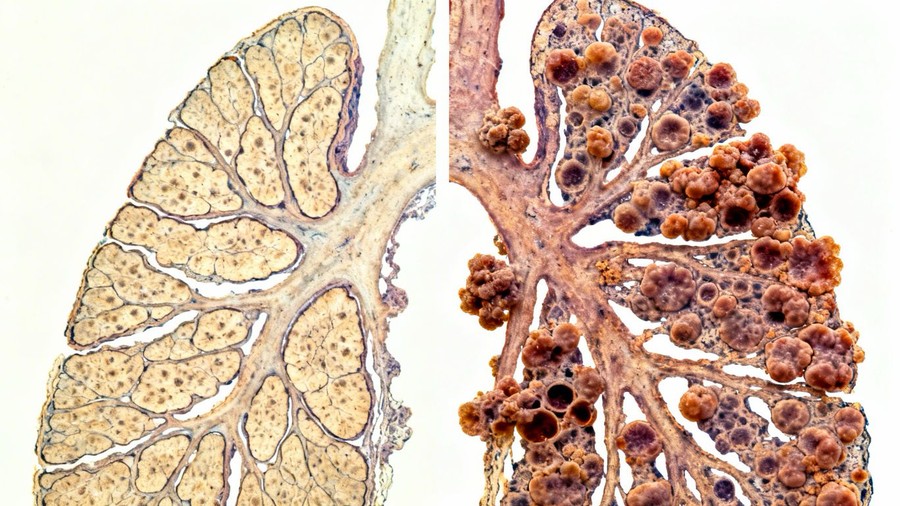

Distinguishing Mesothelioma from Other Lung Cancers

While both mesothelioma and lung cancer can be caused by asbestos, they are distinct diseases. Lung cancer typically originates within the lung tissue itself, whereas mesothelioma arises from the mesothelium, the protective lining. Key differences include:

- Origin: Lung cancer starts in the lung tissue; mesothelioma starts in the lining (pleura, peritoneum, etc.).

- Cell Type: Lung cancers are often carcinomas (adenocarcinoma, squamous cell carcinoma, etc.); mesothelioma is a specific type of cancer of the mesothelial cells.

- Treatment Approaches: While some treatments overlap, the specific staging and therapeutic strategies can differ significantly, requiring specialized care [0546].

Understanding these distinctions is vital for accurate diagnosis and effective treatment planning.